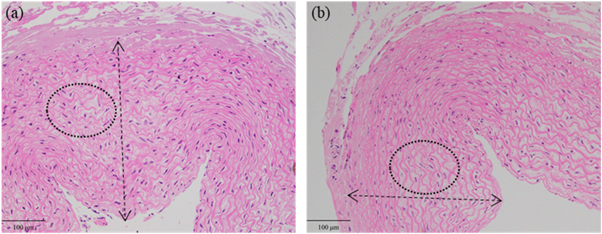

Standard image High-resolution imageWith phantom #2 sonicated with 10 s cooling time, the l was 2 mm and the flow rate was 5 cm s−1. Figures 6(a) and (b) demonstrate the H&E stains of vessels sonicated at 5.3 W in group #1 and 3.5 W in group #3. The vascular wall at 5.3 W was thicker than that at 3.5 W.

Figure 6. H&E stains of the vessels sonicated at 5.3 W (a) and 3.5 W (b). The double arrow indicates the thickness of vascular wall. The deformation of elastic fibers is shown in the ellipse.